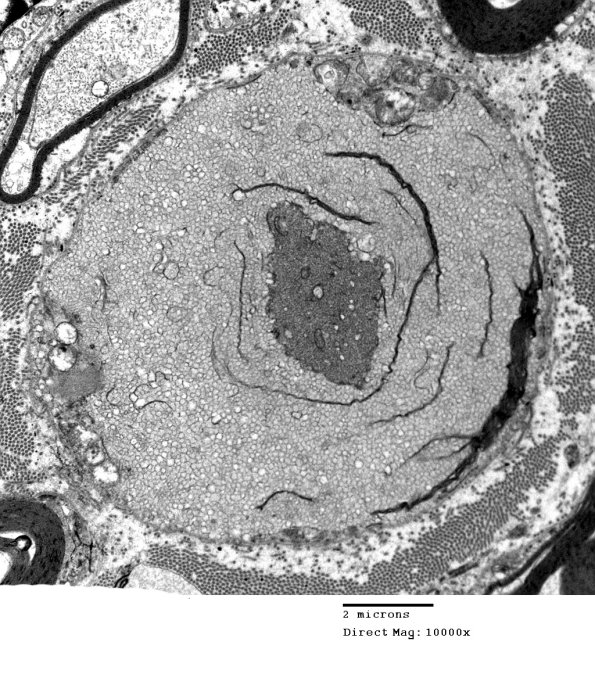

19B10,11 The axon in the center of this abnormal myelin collection is more dense than expected. (electron micrograph)